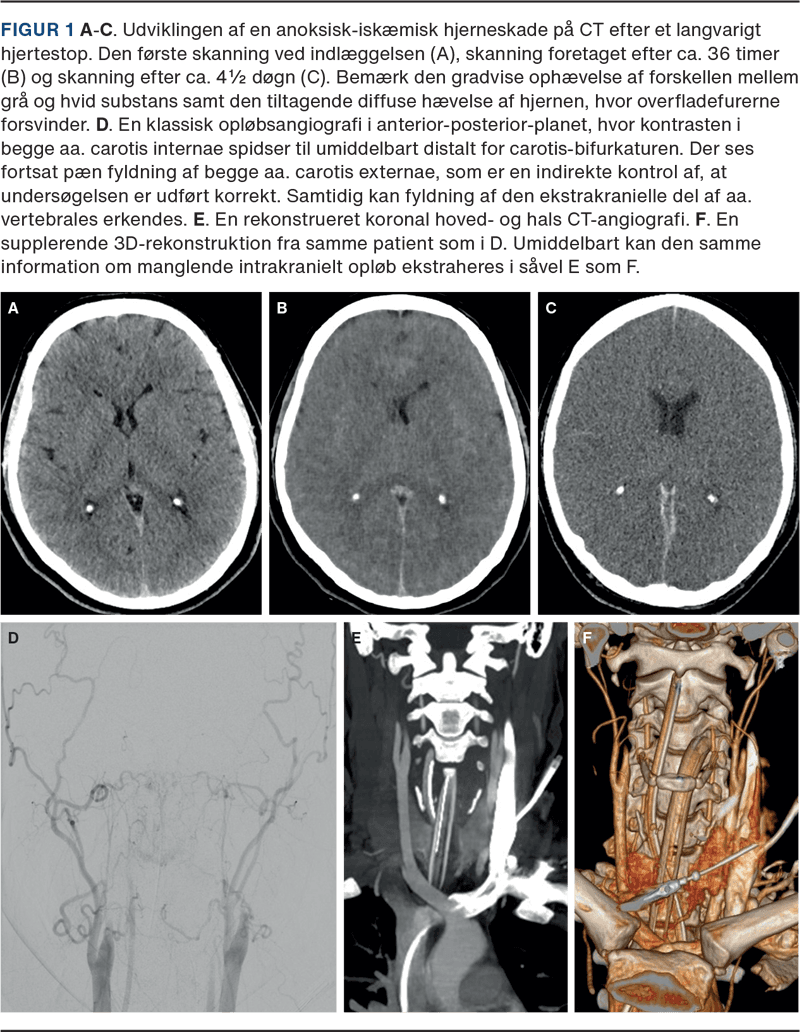

En opløbsangiografi eller en firekars digital subtraktionsangiografi (DSA) er i øjeblikket den eneste tilladte supplerende undersøgelse i Danmark, og den anvendes til at visualisere ophævet cirkulation til hele hjernen. Det diagnostiske kateter indføres via en port i a. femoralis, og anbringes i aorta ascendens. Ved undersøgelsen observeres kontrasttilbuddet i begge aa. carotis internae og a. vertebralis over 15 sekunder. Aa. carotis externae er her en positiv kontrol, som skal fyldes. Såfremt der hverken ses fyldning af a. carotis interna distalt for afgangen af a. ophthalmica eller den intrakranielle del af a. vertebralis, vurderes den cerebrale cirkulation som ophævet. Undersøgelsen gentages efter 15 minutter. Hvis der ved den anden undersøgelse fortsat ikke ses intrakraniel kontrastfyldning af karrene, opfylder patienten de radiologiske kriterier for ophævet cerebral cirkulation.

Opløbsangiografien opfattes som en juridisk nødvendig undersøgelse, og den radiologiske tolkning har derfor været tilsvarende rigid. Patienter, hos hvem der f.eks. ganske kortvarigt ses fyldning af a. carotis interna distalt for afgangen af a. ophthalmica, opfattes som havende cerebral cirkulation. Der indgår ikke en kvalitativ tolkning af, hvorvidt det påviste kontrastflow er fysiologisk eller uforeneligt med cerebral funktion. Selvom opløbsangiografien opfattes som guldstandarden inden for de cerebrale perfusionsundersøgelser, er undersøgelsen afhængig af faktorer som kateterdiameter, kontrastflow, blodtryk og hjertets pumpefunktion. Herudover er undersøgelsen ressourcekrævende, og behovet for eventuel overflytning til et universitetshospital kan have en betydning for, hvorvidt pårørende vælger at samtykke til et donationsforløb. Der er behov for at se på alternativer til vurderingen af den cerebrale perfusion. CT-angiografien er nok den mest lovende modalitet pga. tilgængeligheden uden for universitetshospitalerne og den rutinemæssige anvendelse i hjernedødsdiagnostikken i 11 EU-lande [8, 10, 20-23].

Vi mener, at tiden er moden til en revision af hjernedødskriteriet fra 1990, og at behovet herfor er uafhængigt af, at der nu i Danmark foreligger mulighed for donation efter cirkulatorisk død. Styrelsen for Patientsikkerhed bør sammen med relevante videnskabelige selskaber som Dansk Neurologisk Selskab, Dansk Neurokirurgisk Selskab, Dansk Neuroradiologisk Selskab, Dansk Pædiatrisk Selskab og Dansk Selskab for Anæstesiologi og Intensiv Medicin stå for denne revision. En revision kunne bl.a. omfatte, at CT-forandringerne ved hypoksisk-iskæmisk hjerneskade accepteres som en irreversibel hjernepåvirkning [18, 19]. Den nuværende fremgangsmåde med to kliniske undersøgelser med apnøtest med en times mellemrum kan udfordres, ligesom alternativer til opløbsangiografi som f.eks. CT-angiografi bør overvejes (Figur 1 D-F). Endelig bør kriterierne for børn < 1 år fastsættes.

De danske hjernedødskriterier har ikke været revideret siden indførelsen i 1990. Den billeddiagnostiske udvikling gør, at CT-forandringer ved anoksisk-iskæmisk hjerneskade kan diagnosticeres sikkert, ligesom CT-angiografi vurderes at kunne erstatte DSA. En mere pragmatisk tilgang vil sandsynligvis kunne øge antallet af organdonorer og donerede organer uden at kompromittere den diagnostiske sikkerhed [15].